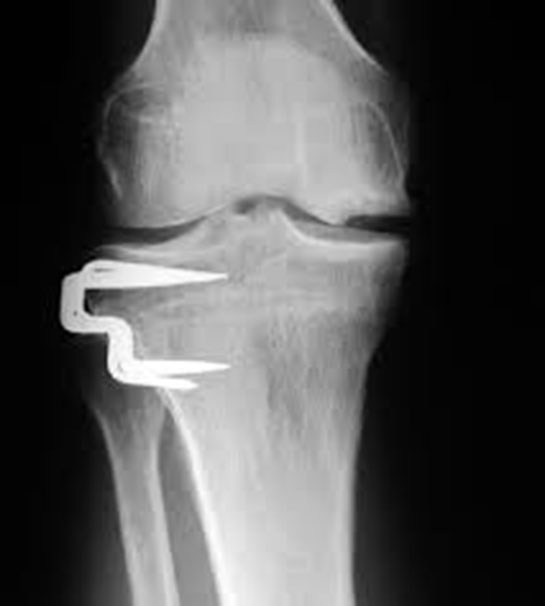

Ameliyat Neden Düşünülebilir?: Ameliyat, diğer tedavi yöntemlerinin yeterli gelmediği durumlarda düşünülebilir. Özellikle, eklemde ciddi yapısal bozukluklar veya ileri derecede kıkırdak kaybı varsa, cerrahi müdahale gerekebilir.